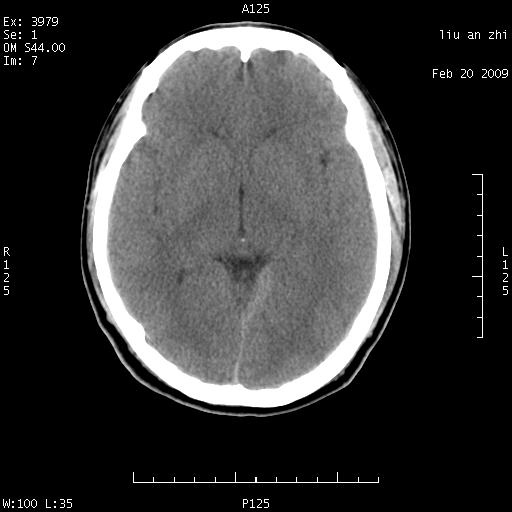

患者:男,32岁 被打伤后3天,自感头昏头痛作头颅ct检查。请大家看一下想什么??

请注意小脑幕!!!

蛛网膜下腔少许出血

考虑---蛛网膜下腔出血

考虑:蛛网膜下腔出血,左侧天幕硬膜下血肿;建议做mri检查